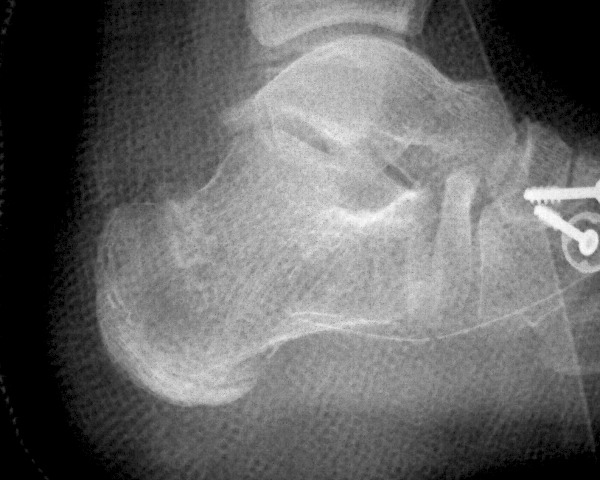

There are many instances when it is appropriate for the foot and ankle surgeon to use bone grafts in order to enhance a patient’s clinical outcome. When it comes to reconstructive osteotomies for angular realignment, arthrodeses and the repair of nonunions and cystic bone lesions, these are often best performed with procedures that take advantage of the many desirable features of bone grafts and, more recently, bone graft substitutes. Before discussing the details of bone graft substitutes, it is helpful to review the bone graft options that are available to the surgeon. These options include: cancellous and/or cortical bone, allogeneic (typically freeze-dried) cadaver bone and autogenous bone. Cancellous bone offers a porous, osteoconductive environment and ease of incorporation. However, it conveys limited structural strength and ability to retain fixation devices. Cortical bone, on the other hand, offers tremendous structural integrity, but it is slow to incorporate in comparison to cancellous bone. Allogenic bone implants offer ease of use, ready availability and provide a wide range of configurations that include cortical and cancellous bone in various proportions. However, despite rigorous measures related to the procurement and preparation of allogeneic tissue products, there remains a very small but real risk of disease transmission and hypersensitivity reaction.1,2 The autogenous corticocancellous bone graft, which is typically harvested from the iliac crest, remains the gold standard for comparison of all other grafting materials. In reconstructive foot and ankle surgery, the calcaneus offers a reliable source of autogenous bone graft material. Unfortunately, however, autogenous sources of corticocancellous bone are limited and there is distinct morbidity associated with harvesting autogenous bone. Banwart et al., performed a meta-analysis of the related literature and observed that use of autogenous iliac crest bone grafts was associated with a 25 to 45 percent complication rate. They also noted that 40 percent of patients related harvest site pain up to five years postoperatively.3 For these reasons, the emergence of bone graft substitutes for enhancement or augmentation of bone grafting procedures, as well as the techniques of bone callus distraction, have proven to be of great service in recent years.